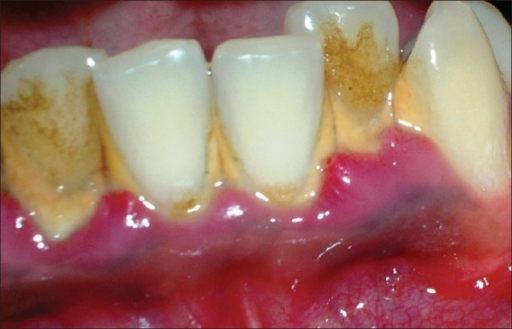

Película blanda y delgada de restos de alimentos, mucina y células epiteliales muertas que se depositan sobre los dientes constituyendo un medio de crecimiento de diversos microorganismos causantes de la caries, es a menudo la primera etapa en carie o enfermedad periodontal.

A mass of filamentous microorganisms and a large variety of smaller forms attached to the surface of a tooth that, depending on bacterial activity and environmental factors, may give rise to caries, calculus, or inflammatory changes in adjacent tissue.

Es conocido que algunos alimentos ofrecen mayor autolimpieza que otros. Alimentos de repostería suelen manchar mucho los dientes y favorecen la proliferación de placa. Otros en cambio, como las verduras y las frutas favorecen la limpieza, en buena parte por un fenómeno de adsorción, según el cual restos de alimentos y placa bacteriana se unen a la superficie de esos alimentos y se arrastran junto a ellos.

If this is not removed, low pH generated by metabolism of bacterial plaque organisms will dissolve the hydroxyapatite mineral phase of tooth tissues and with other inflammatory metabolites, cause irritation and damage to the gingival mucosa.